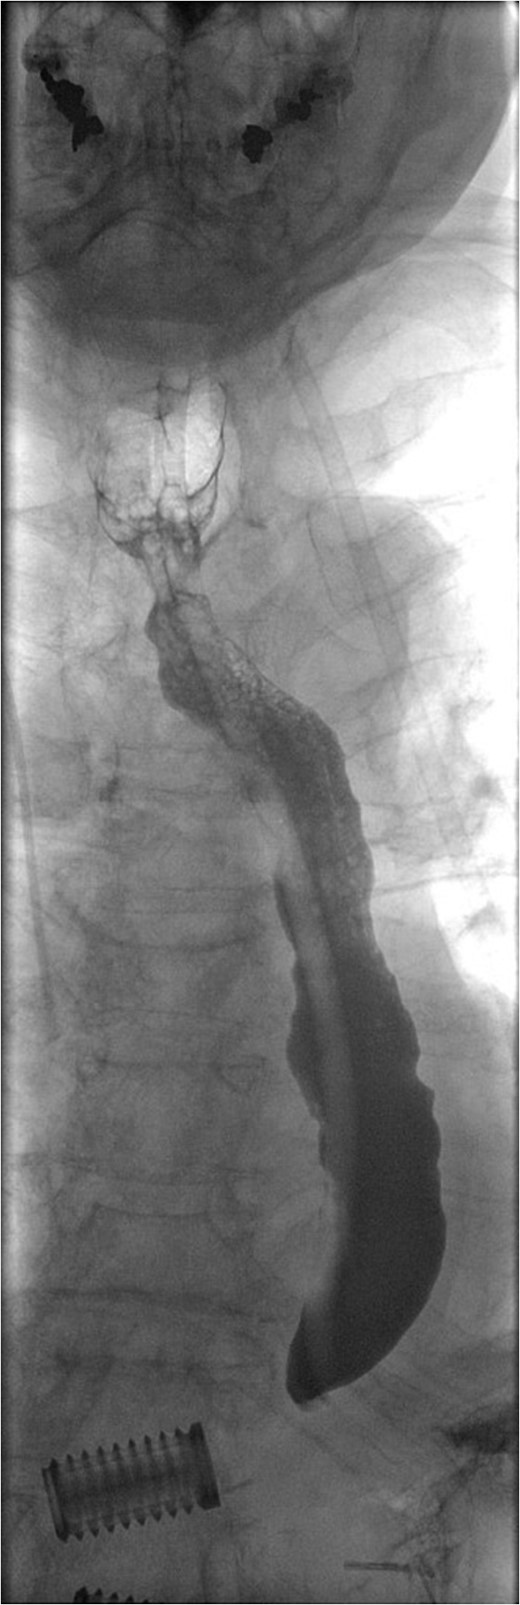

A 69-year-old woman who was previously well, with no history of steroid or non-steroidal anti-inflammatory use, was referred to our unit with an iatrogenic oesophageal perforation. She had undergone a laparoscopic cholecystectomy 5 weeks earlier, complicated by a secondary intra-abdominal bleed requiring laparotomy and splenectomy. The post-operative period was further complicated by small bowel obstruction secondary to internal herniation. This required an emergency laparotomy during which a posterior gastric perforation was identified (Fig. 1). Prior to transfer to our unit, the patient had undergone an upper GI endoscopy and attempted endoscopic placement of a VAC therapy device in order to treat this gastric perforation. Whilst attempting to progress the sponge component of the VAC device, the patient suffered an iatrogenic oesophageal injury. Computed tomography (CT) imaging demonstrated mediastinal emphysema, confirming a full thickness tear of the cervical oesophagus (Fig. 2).

Fluoroscopic image demonstrating contrast entering intraperitoneal drain in proximity to gastric perforation (previous spinal surgery).